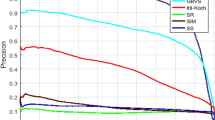

Magnetic resonance imaging (MRI) is the most clinically used and gifted modality to identify brain abnormalities in individuals who might be at risk for brain cancer. To date, automated brain tumor segmentation from MRI modalities remains a sensitive, computationally expensive, and a demanding task. This paper presents an automated and robust segmentation method to enable investigators to make successful diagnosis and planning of radiosurgery by reducing the risk factor and study duration. The proposed system consists of following steps: (1) remove the non-brain part from MRI, (2) estimate saliency map of MRI, (3) use the salient region (tumor) as an identification marker and segment the salient object by finding the “optimal” closed contour around the tumor. The system has been tested on real patient images with excellent results. The qualitative and quantitative evaluations by comparing with ground truths and with other existing approaches demonstrate the effectiveness of the proposed method.